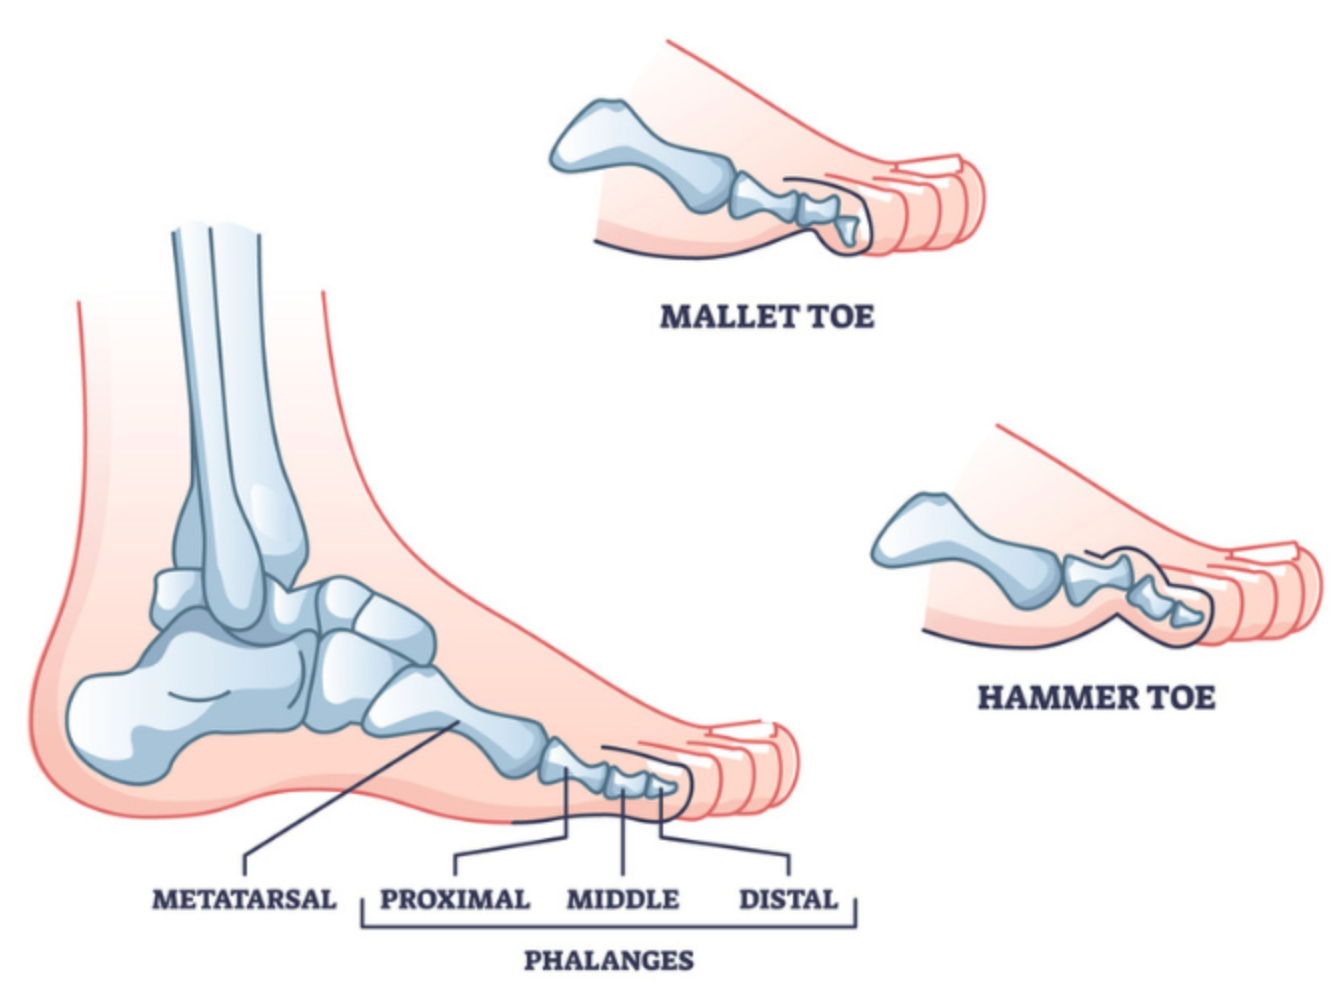

Over time, poor toe alignment caused by tight shoes, lack of proper support, or repeated strain can create a cascade of foot issues. What starts as slight discomfort can evolve into chronic problems like bunions, overlapping toes, or plantar fasciitis.

At first, you might feel mild discomfort, notice redness, or experience fatigue after standing for long periods. Over time, the symptoms worsen, making it difficult to walk, run, or even wear your favorite shoes comfortably. This can escalate to conditions like bunions, hammertoes, or chronic foot pain.